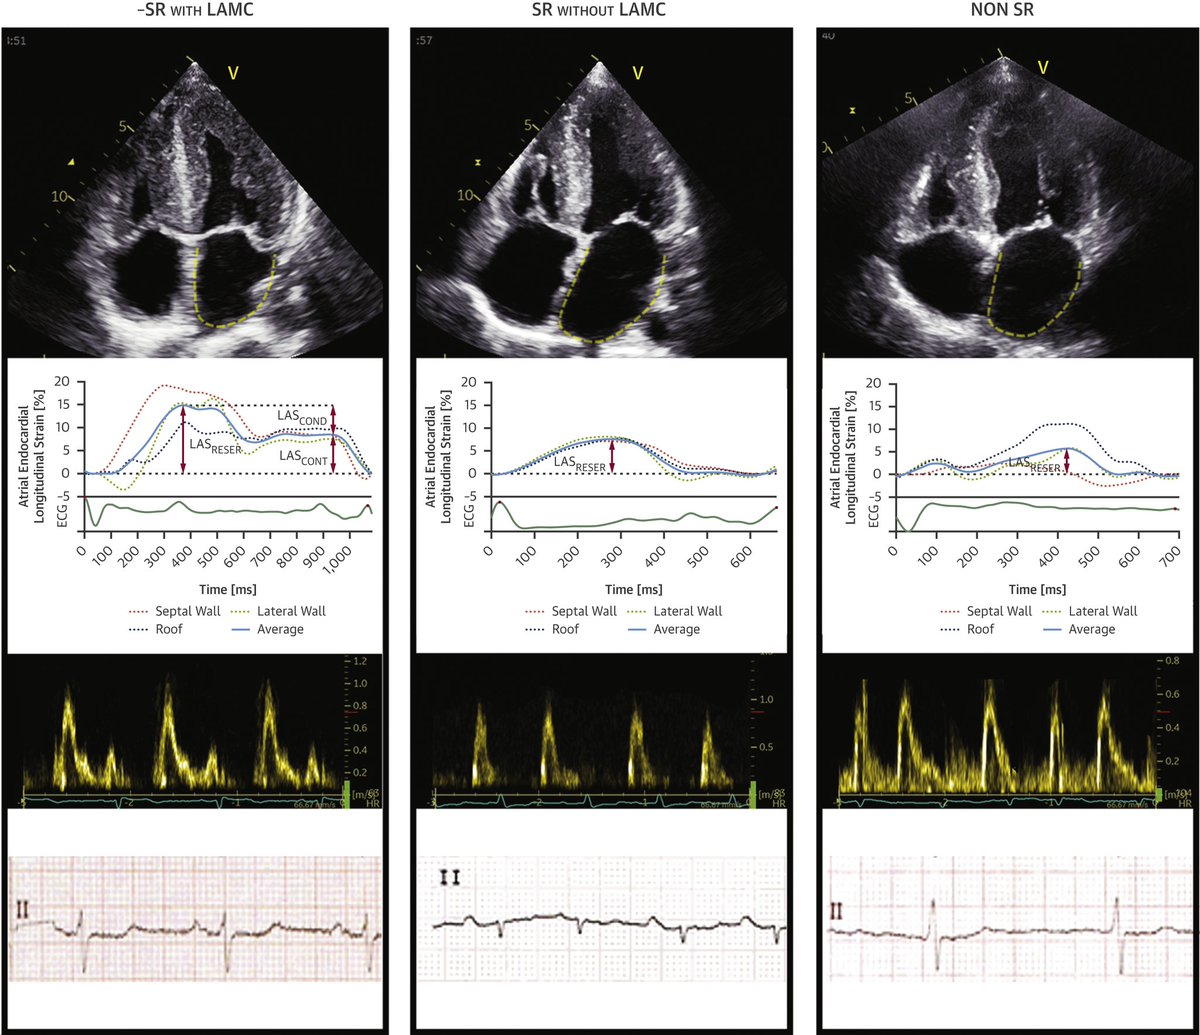

Clinical Importance of LA Infiltration in ATTR #Amyloidosis The LA involvement in ATTR-CM is not limited to chamber dilatation but implies the loss of physiological function (reservoir, conduit & contraction) related to ⬆️ stiffness chamber jacc.org/doi/10.1016/j.… JACC Journals